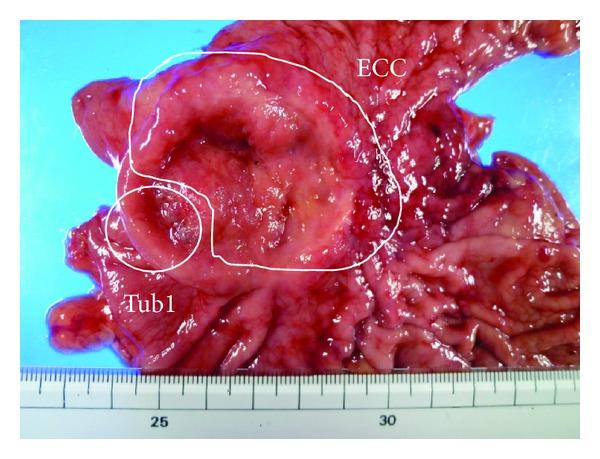

A 69-year-old female presented to our institution with epigastralgia and abdominal distension. Upper gastrointestinal series revealed a 5 cm ulcerative lesion with irregular margins and elevated distinct borders from the angle to the pyloric ring. Gastroendoscopy revealed a Borrmann type 2 tumor. Several biopsied specimens revealed proliferation of small and heterogeneous cancer cells with rich chromatin and fibrous septum with rich vessels at connective tissues, which was confirmed as gastric endocrine cell carcinoma (ECC) on immunostaining with chromogranin and synaptophysin. Furthermore, other specimens revealed atypical cells forming glandular structures, which were confirmed as well-differentiated tubular adenocarcinomas. Distal gastrectomy with D2 lymph node dissection and Billroth I reconstruction was performed. Pathological examination of the gross specimen revealed that adenocarcinoma comprised <10% of all cancer cells. Close analysis of ECC revealed a mixture of small and large cells. According to the WHO 2010 classification of gastrointestinal neuroendocrine tumors, this gastric tumor was diagnosed as neuroendocrine carcinoma. The patient was administered adjuvant chemotherapy with cisplatin and etoposide. One year following surgery, follow-up abdominal CT revealed multiple liver metastases. The patient received the best supportive care but eventually died 18 months after surgery. Here we present this case of gastric ECC coexistent with adenocarcinoma.